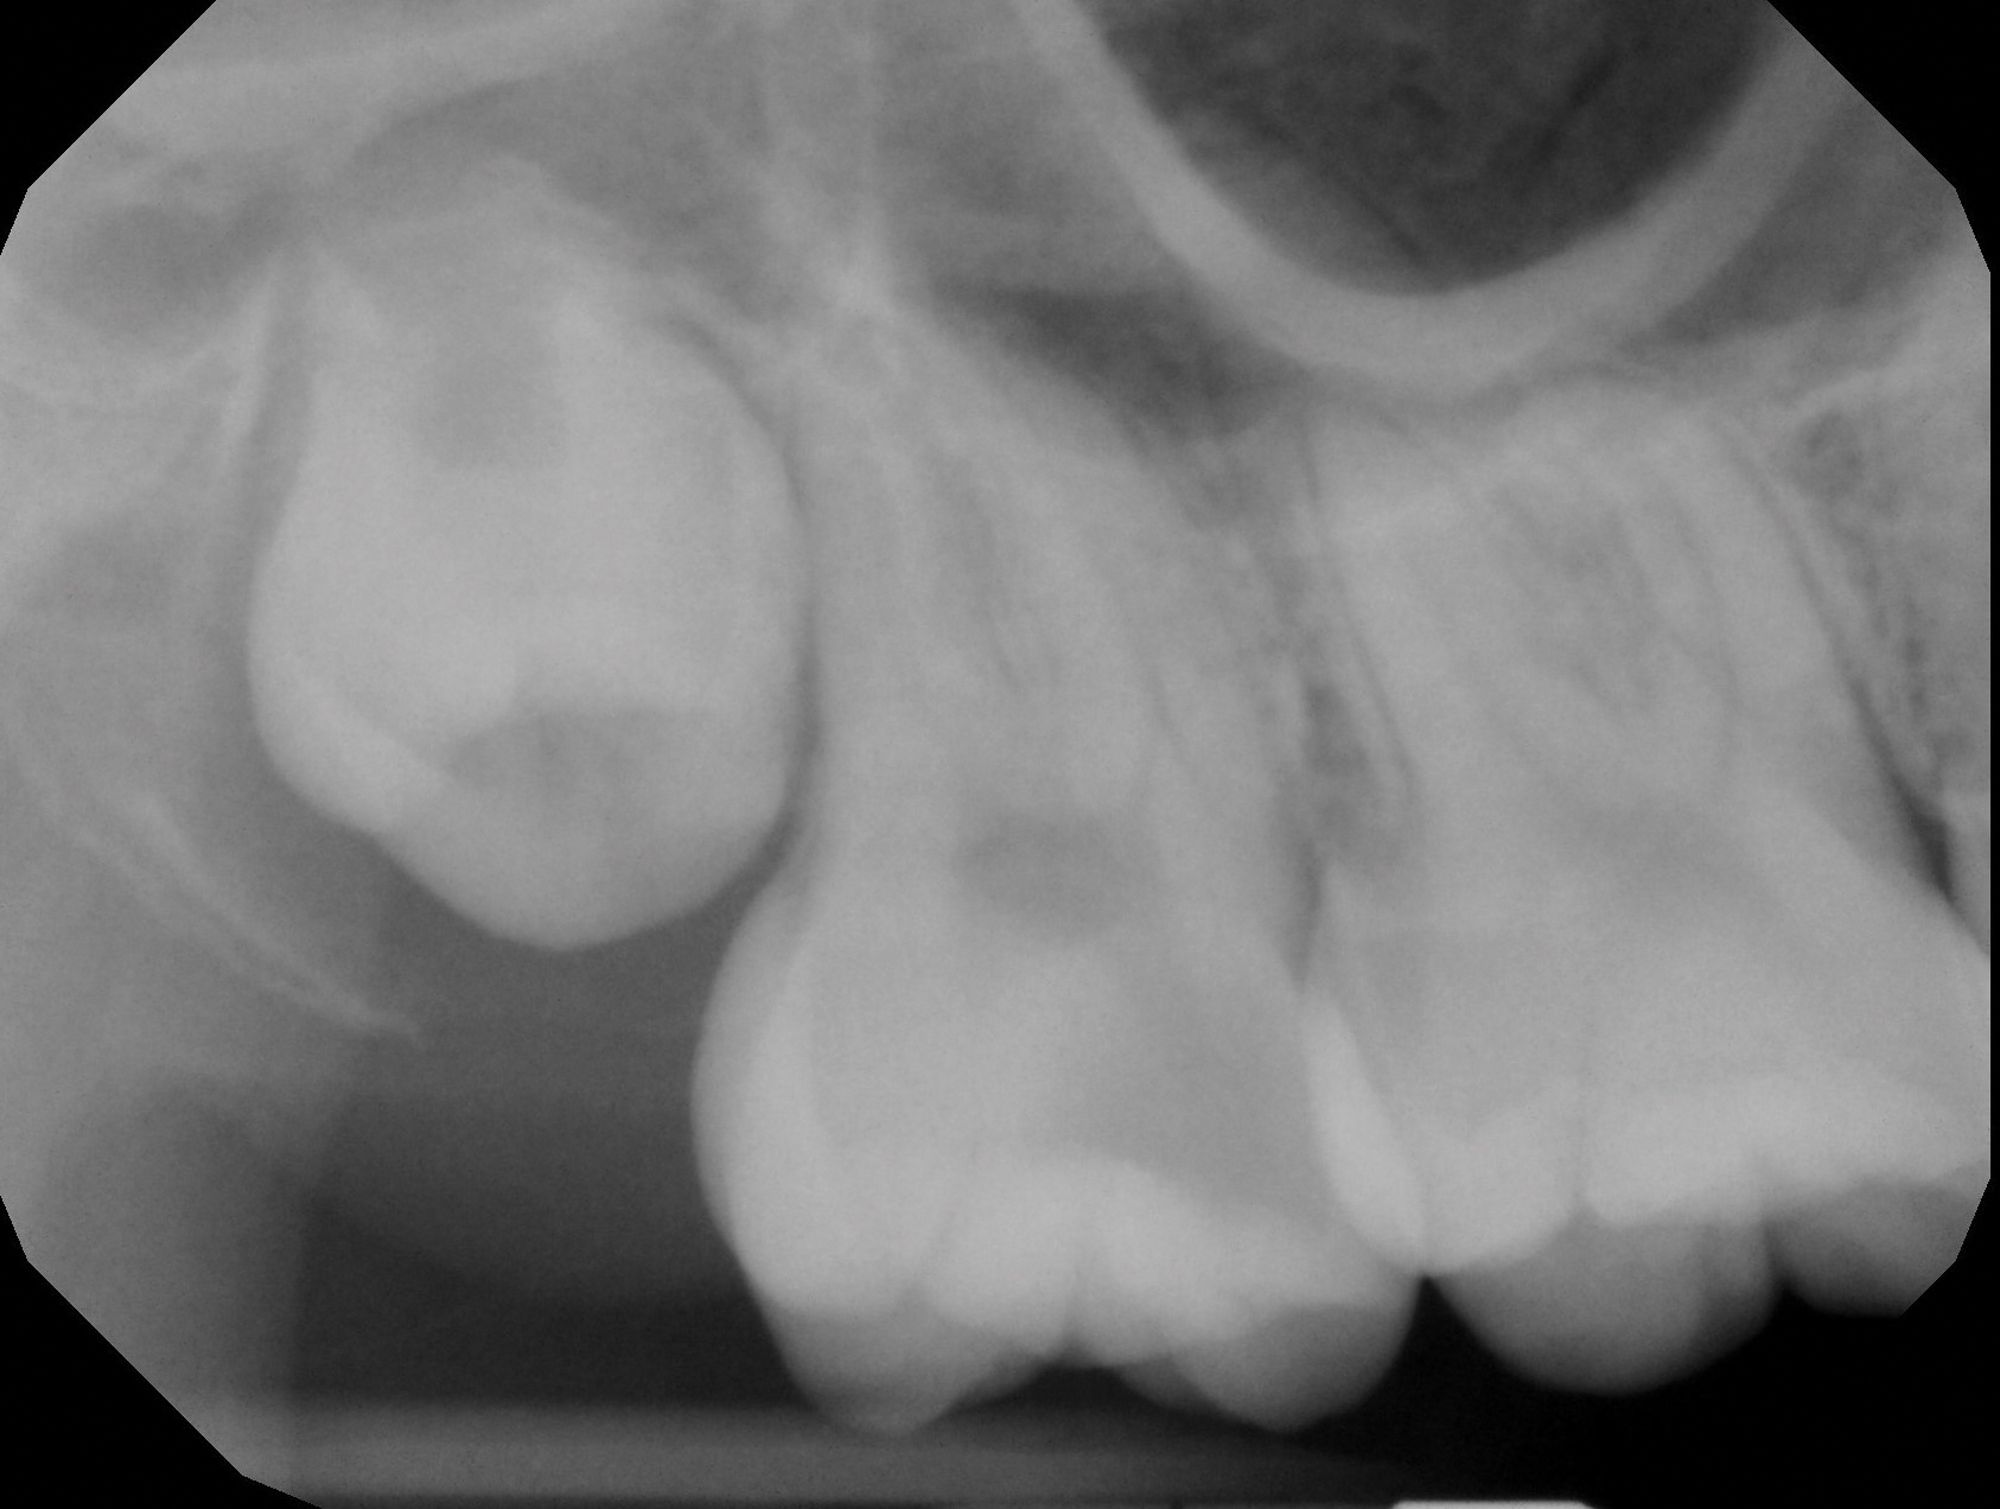

Figure 1A

Figure 1B

Figure 1C. Preoperative images (A and B) depicting deep caries in tooth No. 2 without associated symptoms or clinical testing abnormalities allowed for conservative direct pulp capping to manage the carious exposure (C).